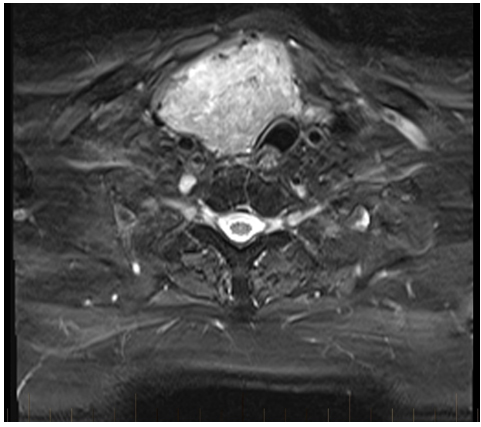

Figure 2. Large goitre causing tracheal deviation and a crescent trachea (MRI)